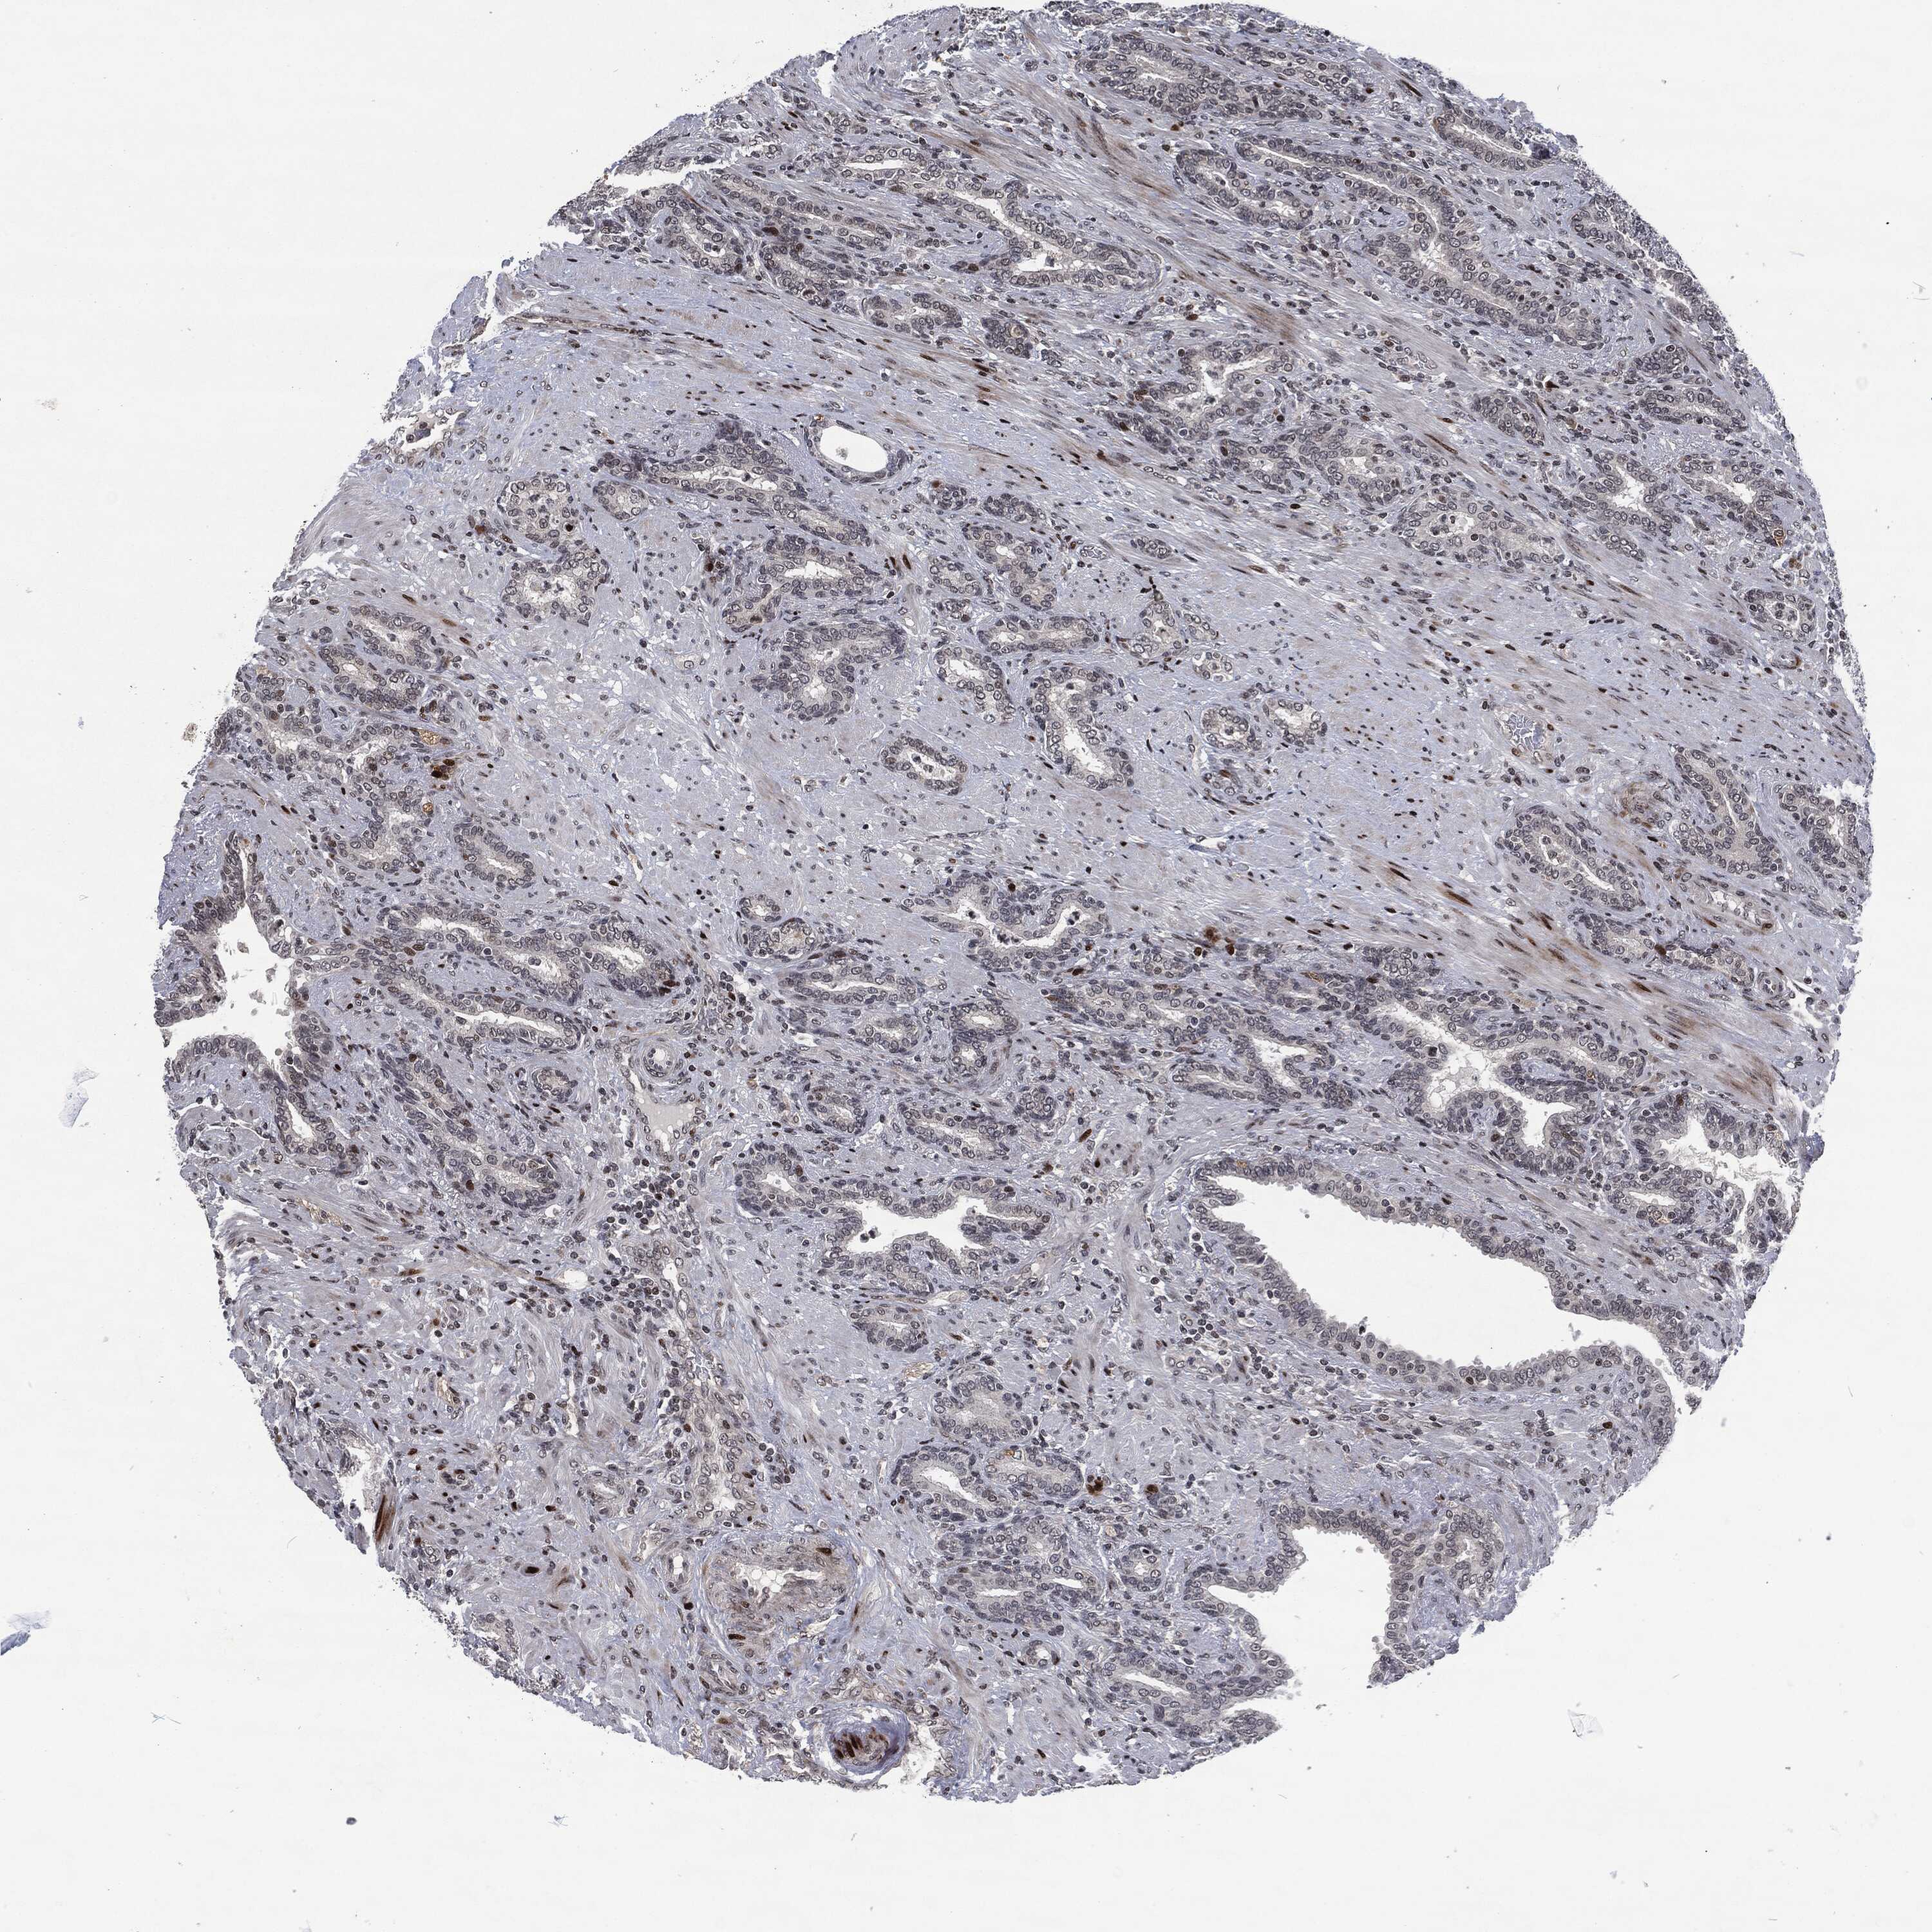

PROSTATE CANCER - Protein expressioni

A mouse-over function shows sample information and annotation data. Click on an image to view it in a full screen mode. Samples can be filtered based on level of antibody staining by selecting one or several of the following categories: high, medium, low and not detected. The assay and annotation is described here.

Note that samples used for immunohistochemistry by the Human Protein Atlas do not correspond to samples in the TCGA dataset.

Antibody stainingi

Antibody staining in the annotated cell types in the current human tissue is reported as not detected, low, medium, or high, based on conventional immunohistochemistry profiling in selected tissues. This score is based on the combination of the staining intensity and fraction of stained cells.

Each image is clickable and will lead to virtual microscopy that enables deeper exploration of all samples and also displays staining intensity scores, fraction scores and subcellular localization as well as patient and tissue information for each sample.

Adenocarcinoma, Medium grade

Adenocarcinoma, Low grade

Adenocarcinoma, High grade

Adenocarcinoma, NOS